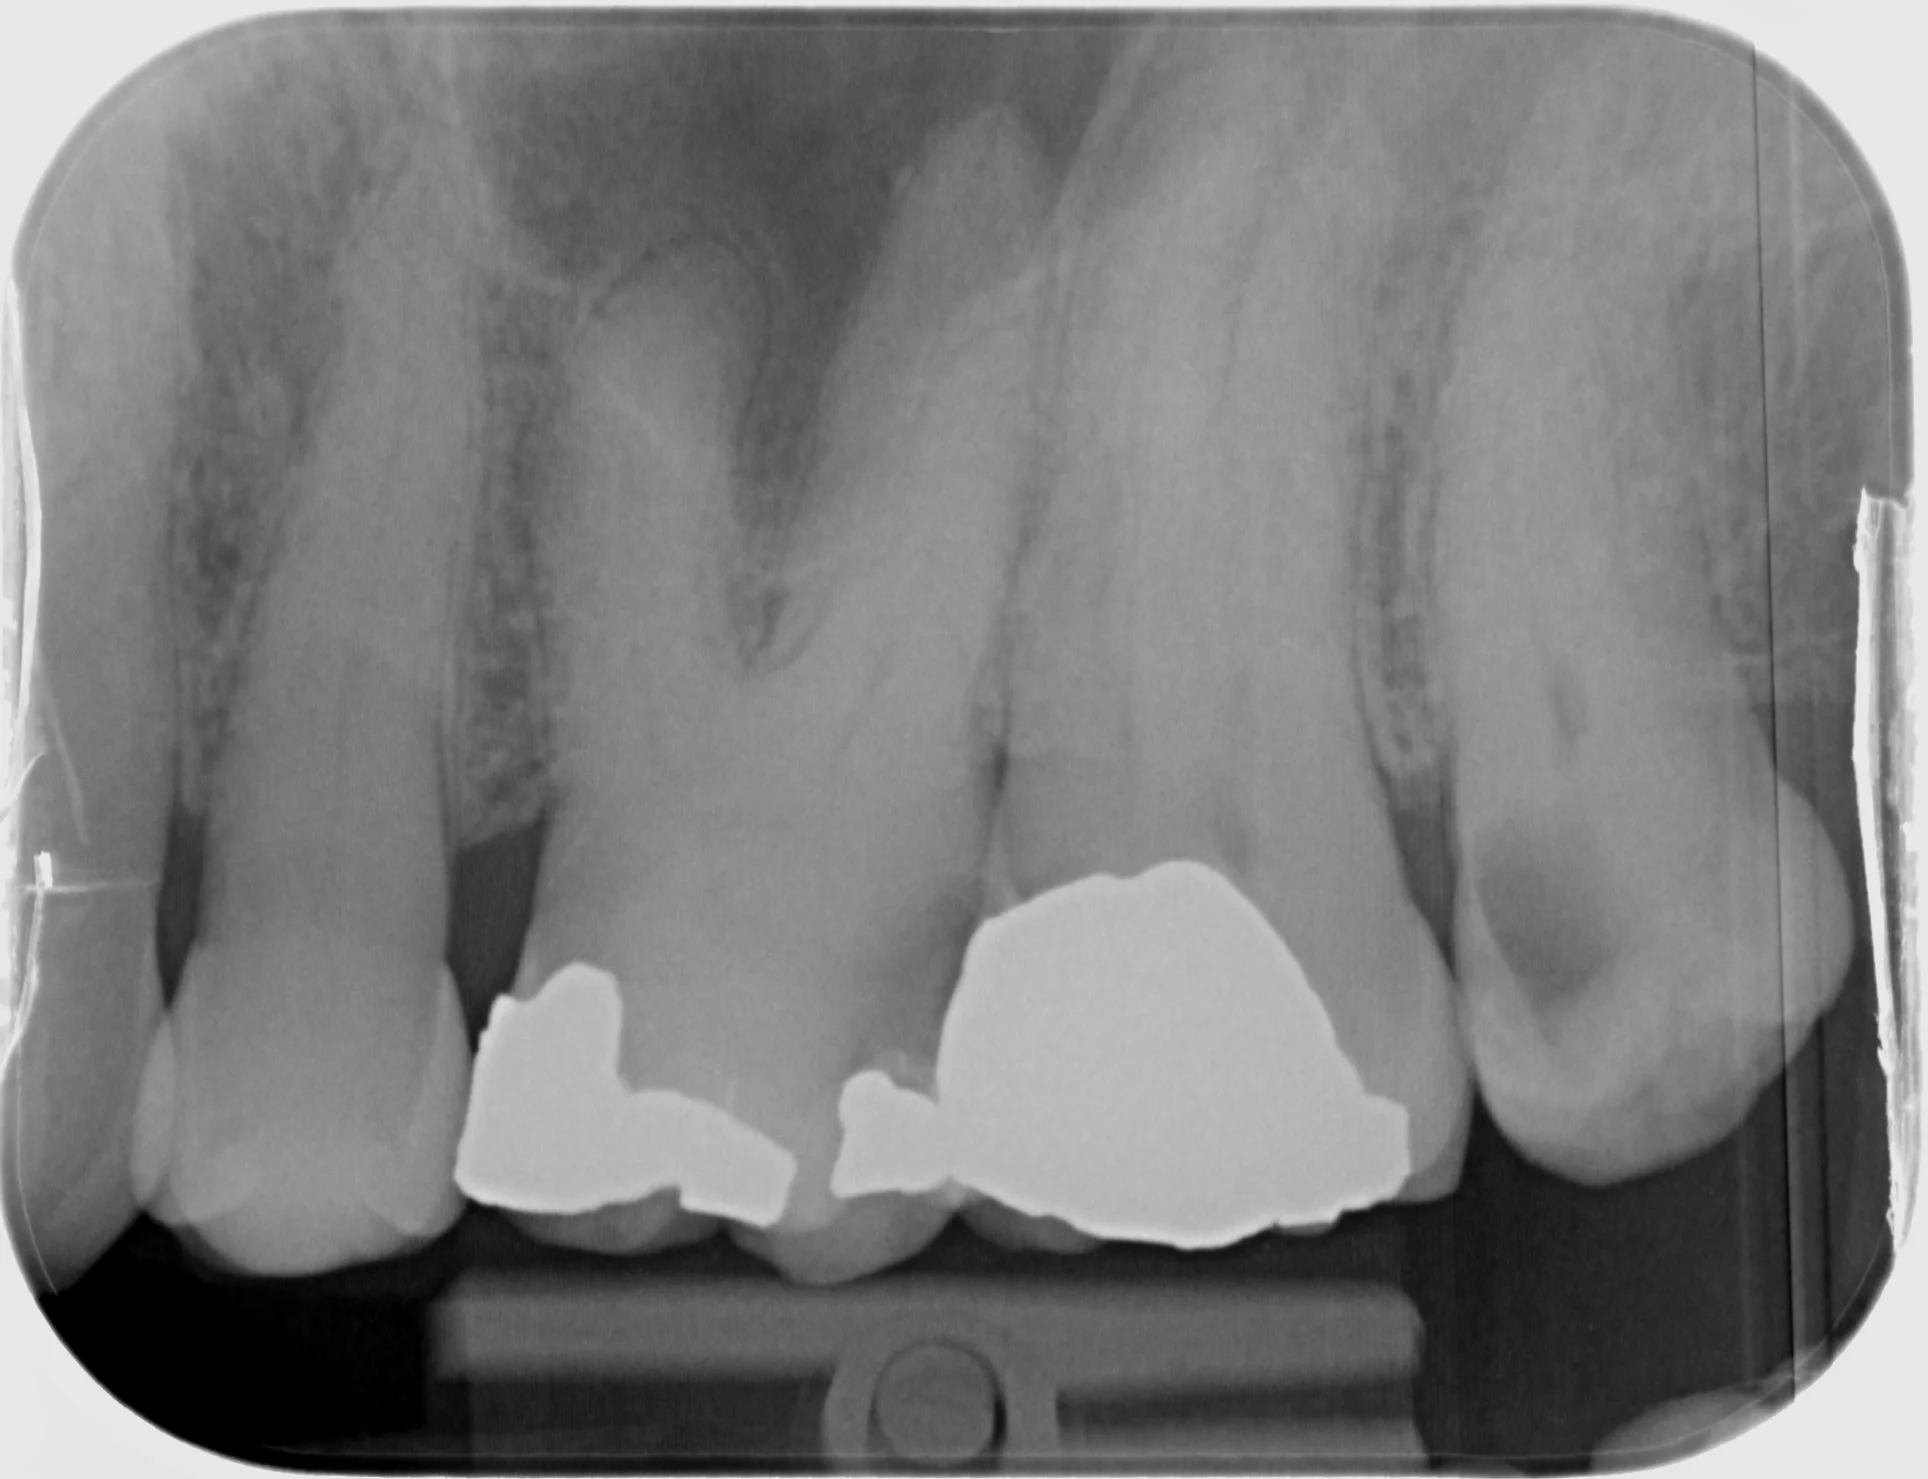

Dental Implants